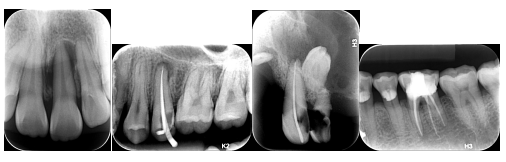

1、数字化牙片机:以摄口内片(牙根尖片)为主,应用软件可做数据分析。